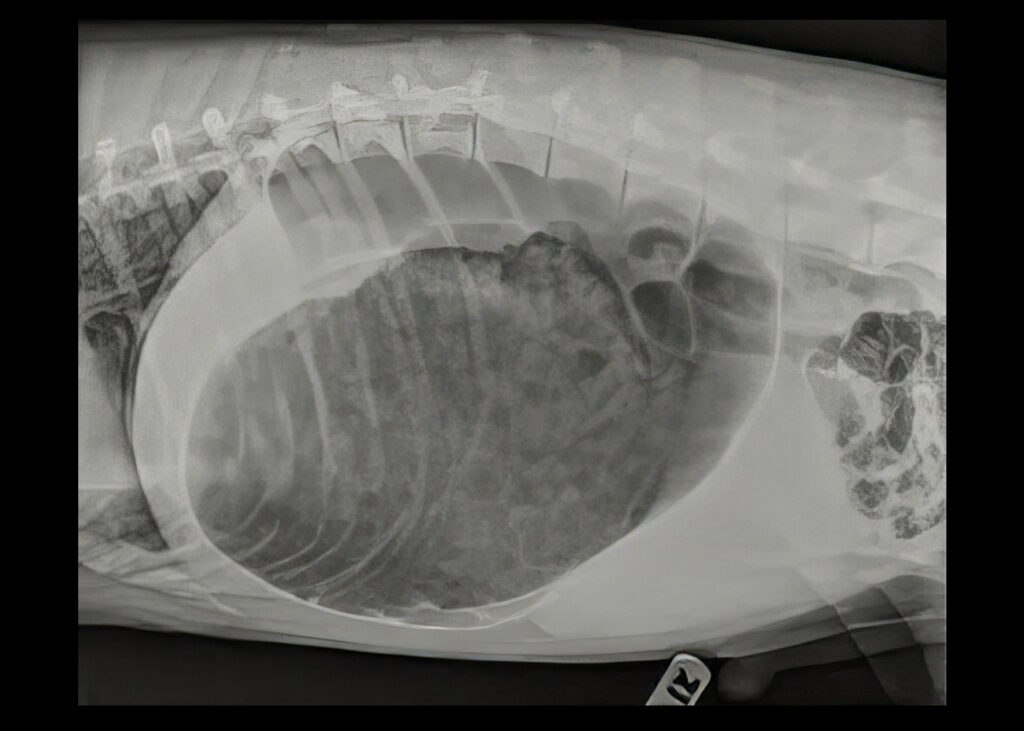

Gastric Dilation-Volvulus (GDV) (Bloat)

This is an extremely serious first aid situation. It occurs when the stomach becomes enlarged through a build-up of gas and then twists along its long axis. Gas then continues to build up because both entry and exit points in the stomach are blocked. This usually causes a very sudden, rapid onset of clinical signs.

- Distended stomach (although this may be difficult to see in deep-chested breeds).